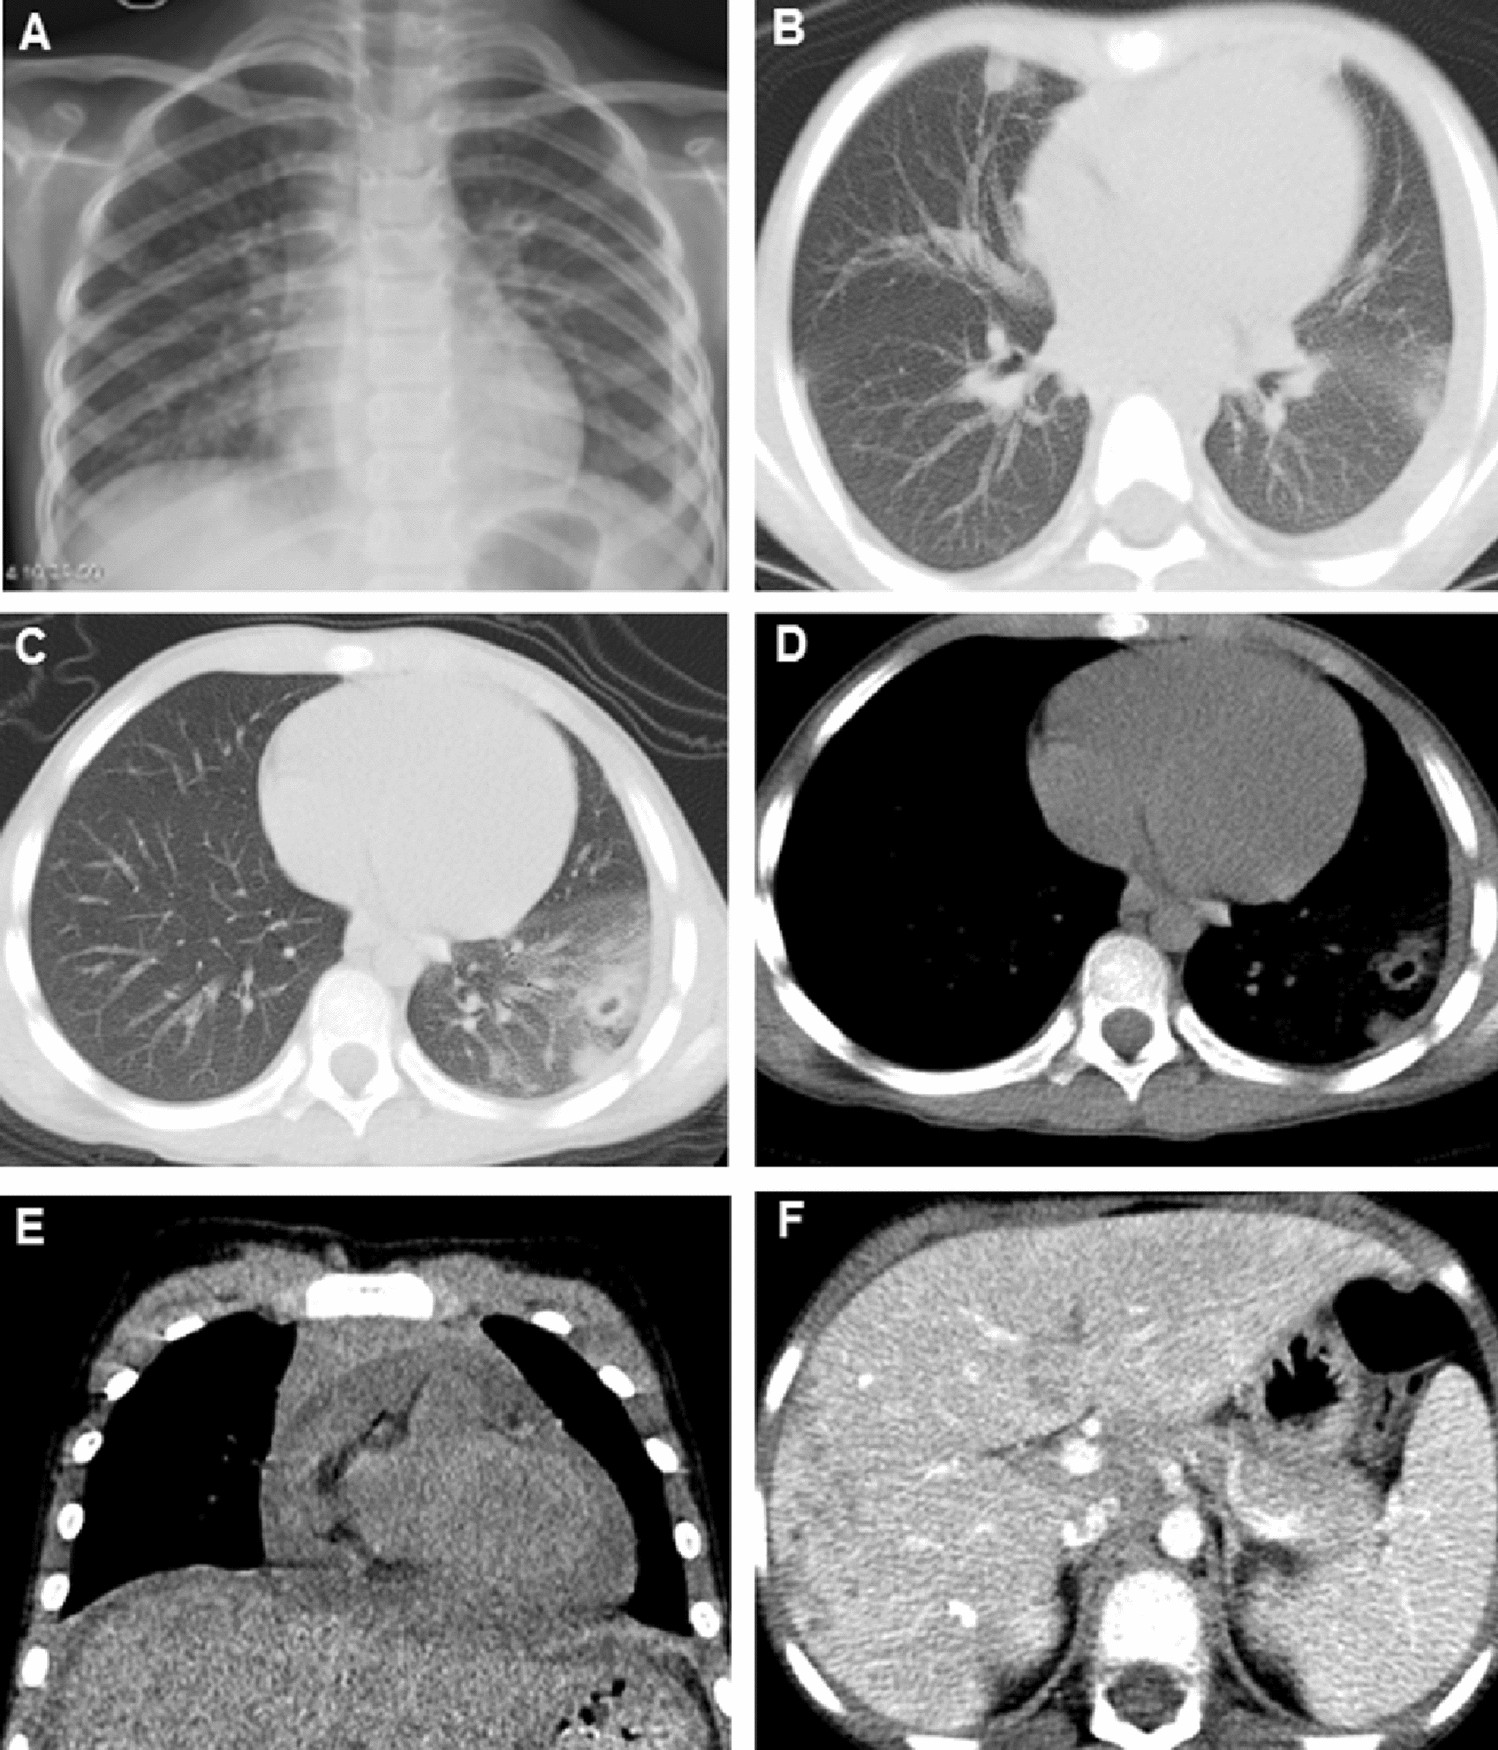

Figure 1

A 7-year-old girl presented with abdominal pain and subcutaneous nodules. (A) Chest X-ray showed pulmonary exudation in the right lower lung lobe; (B–E) Chest CT showed the alveolar opacification and ill-defined nodules in bilateral lungs, pleural effusion in both thoracic cavities; (F) Abdominal CT showed the multiple lesions with low density or calcifications in the liver.